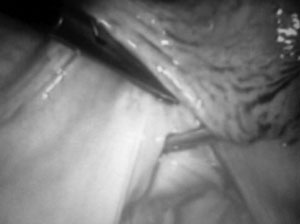

Εικόνα 2. Οι βελόνες Vecchietti

εισάγονται υποπεριτοναϊκά μέχρι την πτυχή ανάμεσα στην ουροδόχο κύστη και την

υποτυπώδη χορδή της μήτρας (uterine rudiment).